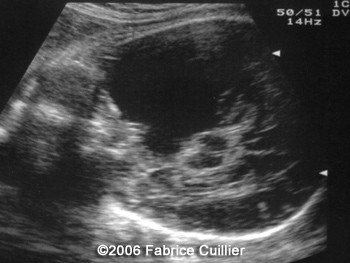

The following images are obtained in a 3rd trimester fetus:

The final diagnosis was: Arachnoid cyst